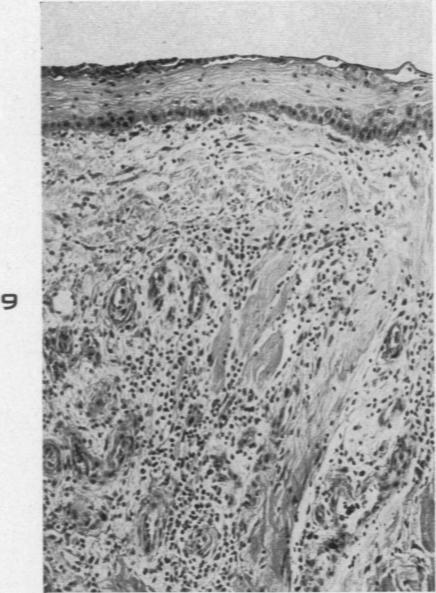

The Pathology of High-Altitude Frostbite.

Am J Pathol. 1947 Mar;23(2):173-87.

Experimental frost-bite in Hanford Miniature Swine. I. Epithelial changes.汉福德小型猪的实验性冻伤。I. 上皮变化。

Br J Exp Pathol. 1989 Feb;70(1):41-9.